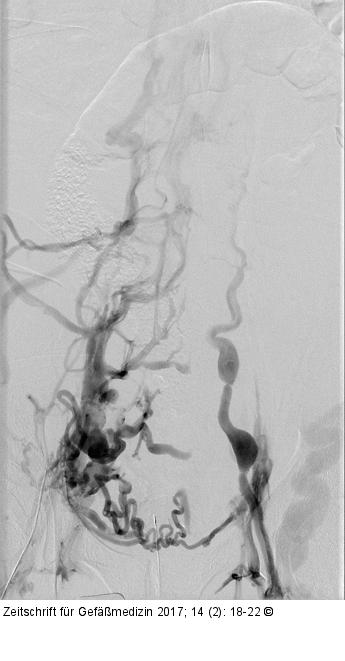

Abbildung 2: Phlebographie Aszendierende Phlebographie des Patienten mit angiographischem Nachweis der venösen Obstruktion der Beckenstrombahn bds.; ausgeprägter Kollateralkreislauf. |

Aszendierende Phlebographie des Patienten mit angiographischem Nachweis der venösen Obstruktion der Beckenstrombahn bds.; ausgeprägter Kollateralkreislauf. |